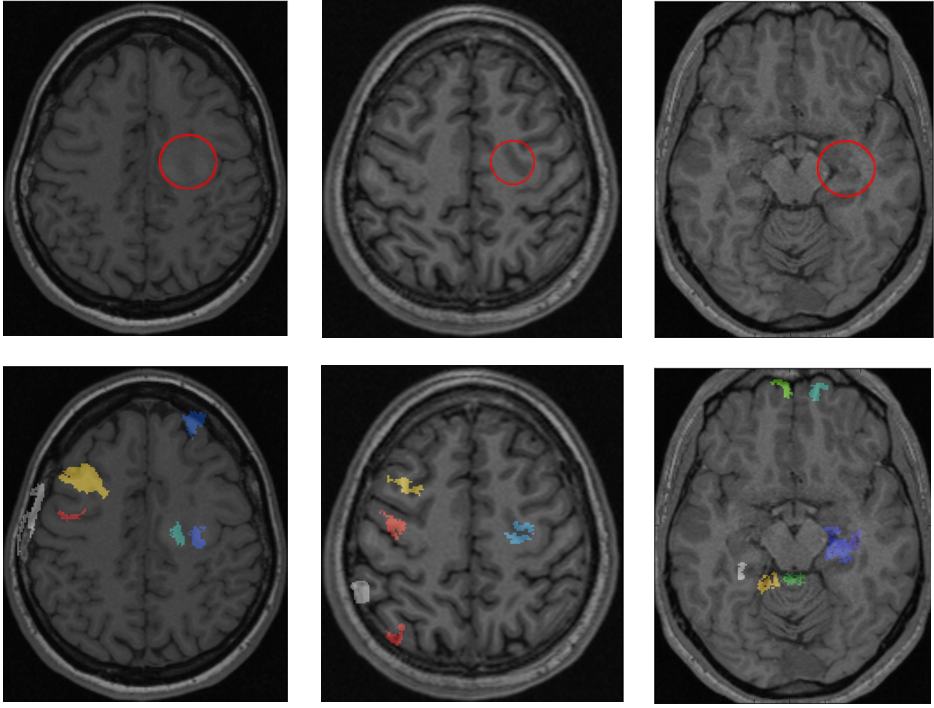

Figure 2: First row: pathological slices of patient A, B and C respectively. The true lesions are outlined in red circles. Second row: Maximum Intensity Projections of the cluster maps onto the same slice as in the first row. The maps are reported for a p-value = 0.003. Note that some clusters appear outside of the brain volume as a result of the MIP projection. Note also that when MIP is used, multiple clusters can appear jointly on the projection, hence the number of false positive clusters on the visualization can be smaller than the reported number in the table below.

Table 1 reports the true lesion detections/clusters and the number of false positive clusters(clusters that were detected by the system but were not considered epileptogenic by the neurologist are considered false positive in this application). The results show that both rSNN and sDA perform adequately and manage to detect the lesions. rSNN, however, outputs less irrelevant clusters (only one epileptogenic lesion was pointed out per patient by the neurologist). An important step of evaluation is to visualize the output cluster maps. Figure 2 demonstrates the maximum intensity projections of the detected clusters onto 3 slices of interest for patients A, B and C. The true lesion locations are outlined in red circles. The maps were obtained for a p-value = 0.003, a threshold which allowed a clear detection of the lesions. This threshold can be varied by a physician allowing to find anomalies on different scales. As we can see, the true lesions (the ground truth is highlighted in red circles) are well detected while some of the false detections (at the brain and skull interface) can be easily eliminated by a trained eye or by post-processing the cluster maps based on geometric features. Some reported clusters may also correspond to true anomalies that are either benign or were not reported as epileptogenic by the neurologist.